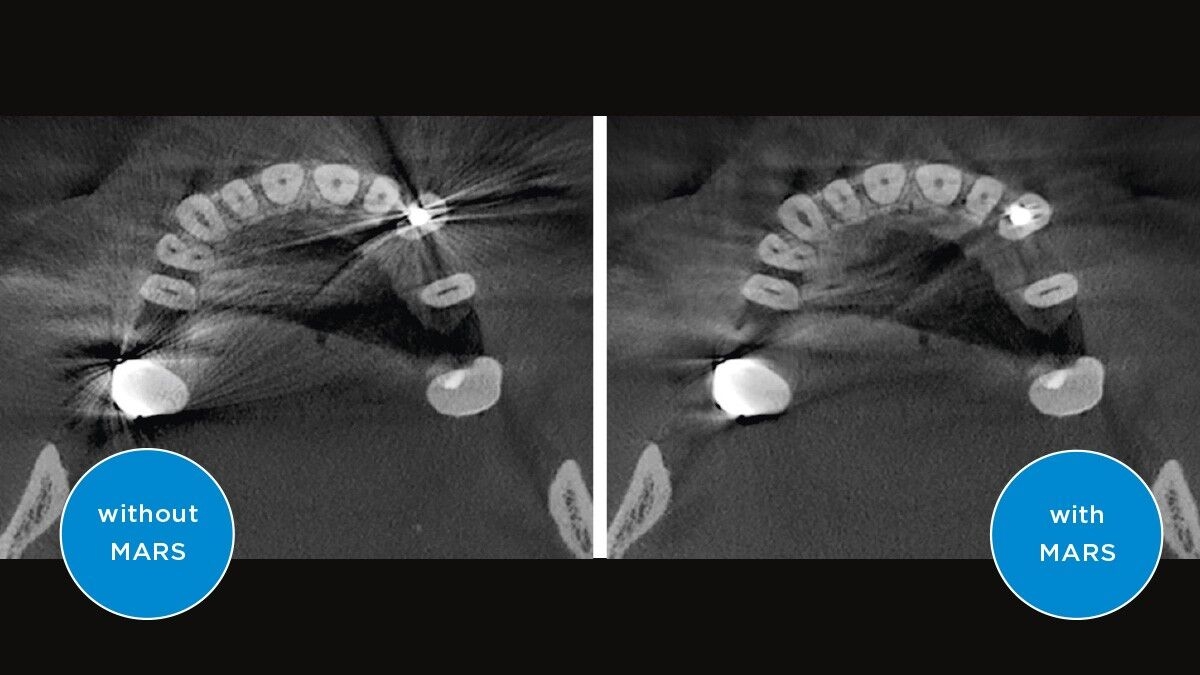

MARS

MARS automatically detects and reduces metal artifacts in 3D images using innovative algorithms

MARS – Metal Artifact Reduction Software

Metal artifacts are a challenge in 3D X-ray imaging. Radiopaque objects create shadowing and streaking effects during the three-dimensional reconstruction and as such interfere with the findings. MARS automatically reduces metal artifacts and facilitates the diagnosis.

We have tested MARS and we love it. We see so much more that we couldn't imagine not using MARS.